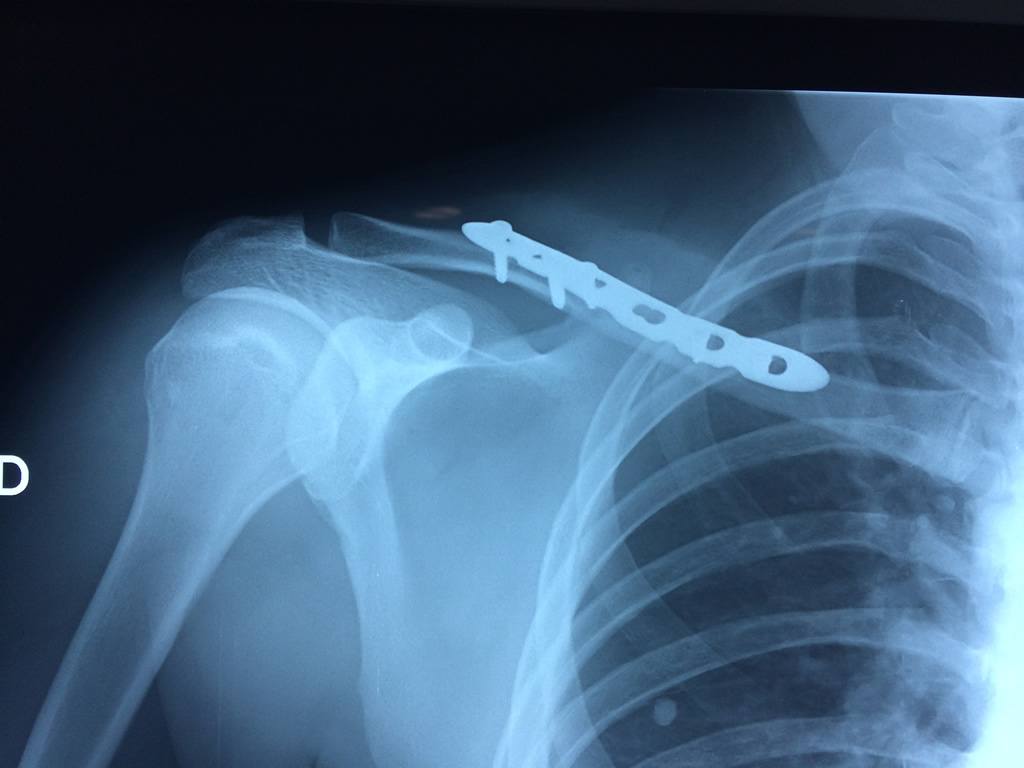

Cirugía de Fémur - Clavícula

La clavícula es un hueso largo, con forma de "S" itálica, situado en la parte anterosuperior del tórax. Junto con la escápula forman la cintura escapular. Se puede palpar por toda su longitud y se extiende del esternón al acromion de la escápula, siguiendo una dirección oblicua lateral y posterior.